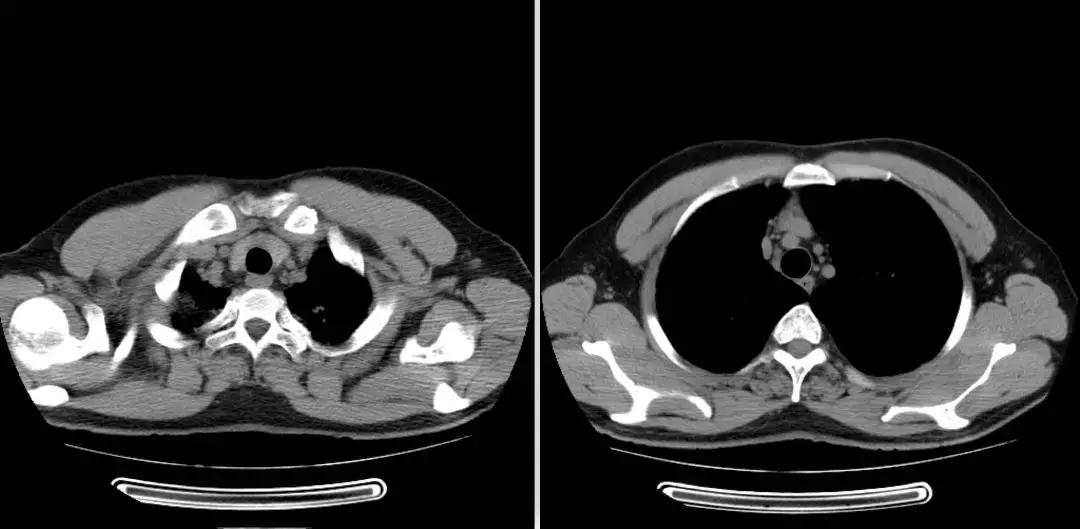

2018-01-22行支气管镜检查:示两侧支气管粘膜充血明显,可见少量白色分泌物,充分吸引;于左下叶生理盐水20ml灌洗2次,回吸收均约10余ml;左上叶、左下叶刷检,刷片共6张。(气管镜报告如下图)。

隆突 右上叶

右中叶 右下叶

左上叶 左下叶